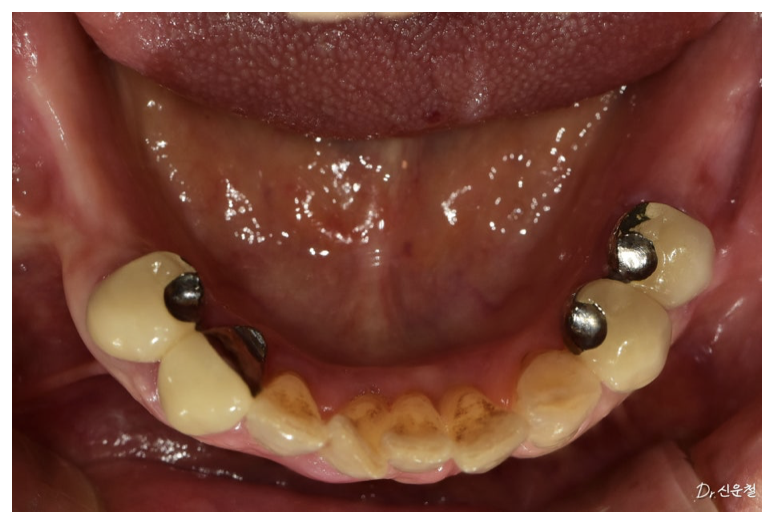

아래쪽에 부분 틀니를 사용하고 있었는데

앞니와 작은 어금니 몇 개만 남아 있는 상태였습니다.

문제는 틀니를 지탱하던 앞니의 상태였습니다.

검사를 해보니

치아 상태가 좋지 않아 발치를 고려해야 하는 상황이었습니다.